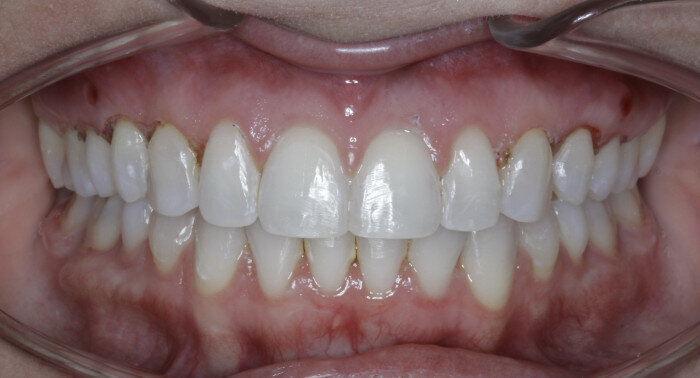

Once the intrusion has been completed, the TADs are tied to the wire and vertical elastics are used to close the bite without relapse of the intrusion. If buccal crown tip is seen, owing to the movement created by the intrusion, a power chain torquing sling is used to encourage lingual crown tipping and to prevent flaring of the incisors (Fig. 9). Once the case has been completed, the appliance is removed and a gingivectomy is performed to idealise the tissue shape and the final contours are made to the hard tissue (Figs. 10–12, end of treatment).

Fig. 10

Fig. 11

Fig. 12